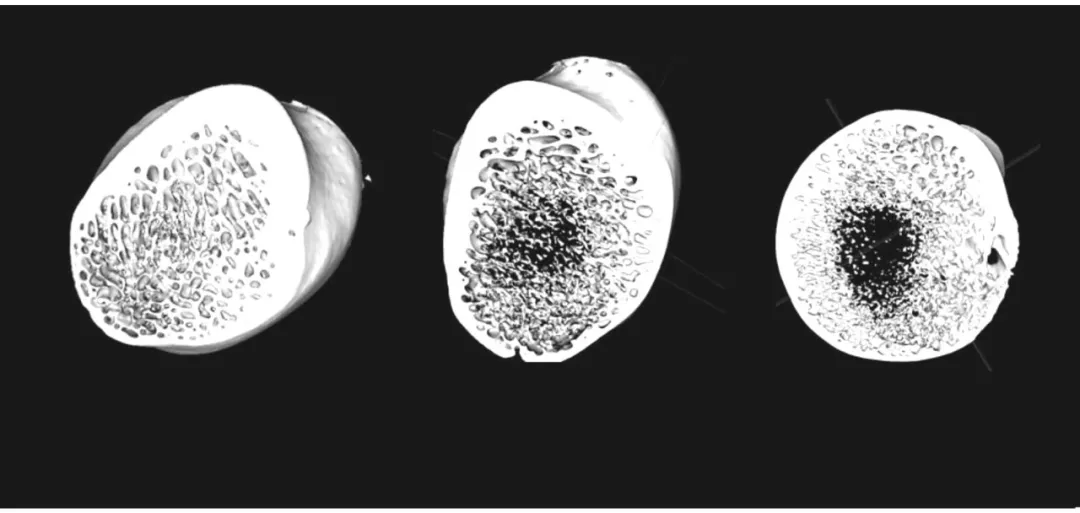

假手術組(左)與去勢 4 個月組(中) 及去勢 12 個月 組(右) 腰椎松質骨的三維重建圖像。圖片顯示,去勢 12 個月組的骨小梁較其他兩組明顯稀疏,孔隙率增加,水平方向骨小梁減少,局部有較大的骨小梁空隙形成。圖片源于文獻【1】。

假手術組(左)與去勢 4 個月組(中)及去勢 12 個月 組(右)股骨頸處松質骨的三維重建圖像。圖片顯示,去勢 12 個月后,股骨頸處松質骨有空腔形成,骨小梁明顯變細,皮質骨壁變薄。圖片源于文獻【1】。